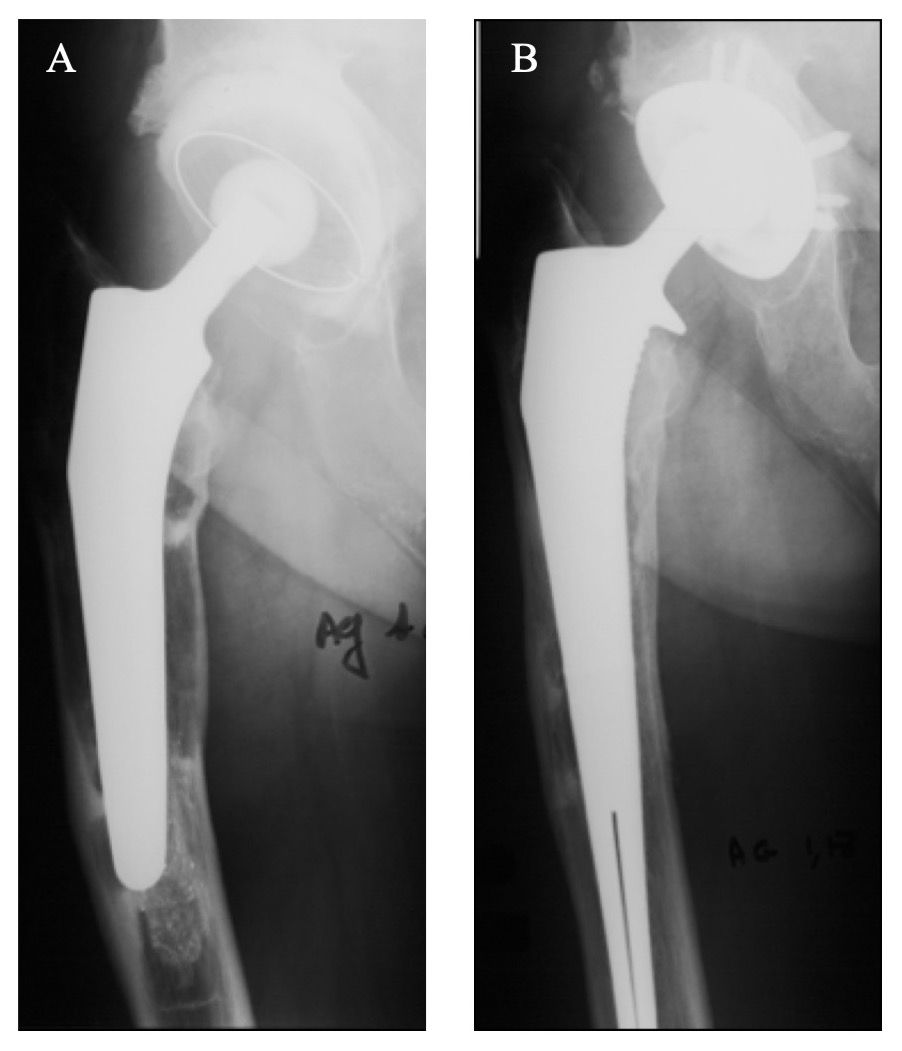

RLs were observed in a total of 38 hips (20%): limited to one Gruen zone in 23 hips (12%), two Gruen zones in 14 hips (8%), and three Gruen zones in only 1 hip (1%). Most RLs were observed in proximal Gruen zones 1 (n=27), 7 (n=13) and 8 (n=4), with very few in middle Gruen zones 2 (n=5) and 6 (n=4) and only one at distal Gruen zone 12. It is worth noting that the distinction between RLs and bone loss sequelae is difficult to ascertain for revision THA stems, particularly if morselised bone graft was required to fill bone defects. Stem migration ≥5mm, compared to the immediate post-revision radiograph, was observed in 7 hips (4%), of which 1 had a Paprosky grade 2, 2 had a grade 3A, 3 had a grade 3B and 1 had a grade 4. The authors observed that, in cases with pre-revision femoral granulomas and osteolysis, post-revision radiographs showed considerable femoral bone reconstruction with nearly complete filling of defects (Figs. 4, 8, 9).

Though aseptic loosening is the most common reason for revision THA (Fig. 2), the indications for revision using HA-coated stems include several other diagnoses as: intertrochanteric fracture with cerclage of the greater trochanter, periprosthetic fracture, tumor resection, extensive osteolysis, and reimplantation in one- or two-stage exchange arthroplasty for the treatment of chronic infection at the site of THA. Implant revision for pain and severe stress shielding has also been discussed by some authors.